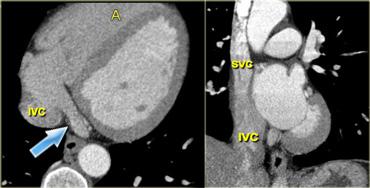

Tái tạo mặt cắt ngang (trái) và mặt cắt vành chếch (phải) của tim, mô tả nhĩ phải và các mạch máu chính dẫn vào: xoang vành (mũi tên xanh) và tĩnh mạch chủ trên và dưới. IVC=tĩnh mạch chủ dưới, A=trước, SVC=tĩnh mạch chủ trên

Nhĩ phải

Giải phẫu tim sẽ được trình bày theo thứ tự dòng máu bình thường: từ phải sang trái.

Trong điều kiện bình thường, thuốc cản quang được tiêm vào tĩnh mạch – thường ở cánh tay – và đi đến nhĩ phải qua tĩnh mạch chủ trên.

Nhĩ phải nằm ở vị trí trước bên trong tim, và nằm phía dưới nhĩ trái.

Tĩnh mạch chủ trên đi vào qua trần của nhĩ phải.

Tĩnh mạch chủ dưới đi vào nhĩ phải từ phía dưới, gần vách liên nhĩ.

Một cấu trúc khác dẫn máu về nhĩ phải là xoang vành (hệ thống dẫn lưu tĩnh mạch của các động mạch vành), đi vào phía trước và ngay bên trái của tĩnh mạch chủ dưới.